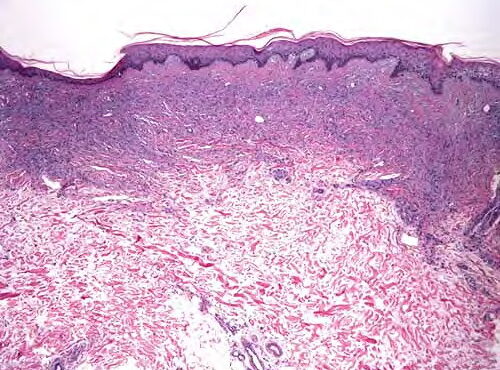

Dermoid_cyst =كيسة جلدانية Dermoid Cyst Dermoid cysts are subcutaneous cysts that usually are present at birth. They occur most commonly on the head, mainly around the eyes, and occasionally on the neck. When located on the head, they often are adherent to the periosteum. Usually they measure between 1 and 4 em in diameter. Histopathology. Dermoid […]